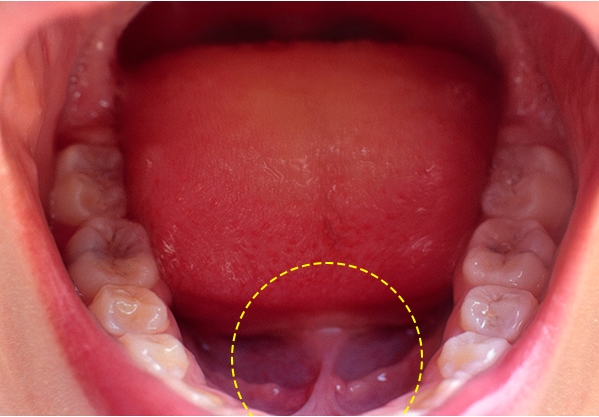

2. 설소대

설소대는 혀 아래 부분과 점막 부분을 잇는 띠 모양의 힘살을 말하며

진단 시 설소대 단축증과 같은 설소대의 이상이 발견될 경우에는 치료가 필요할 수 있습니다.